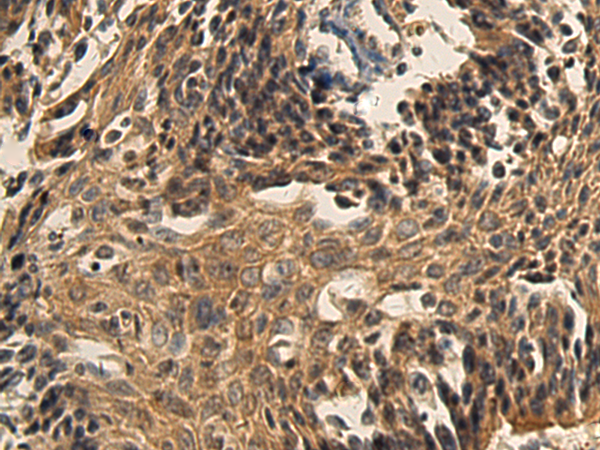

The image is immunohistochemistry of paraffin-embedded Human lung cancer tissue using (XAGE2 Antibody) at dilution 1/140.

IHC dilution:1:100-1:300